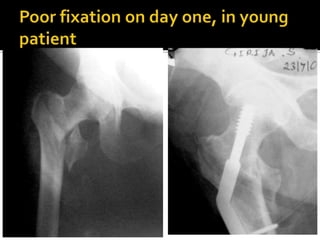

If neither have been followed, it is not right to

blame the nail or the device or to look for a new

design

Factors in our control:

1. Correct choice of implant

2. Correct execution of surgery